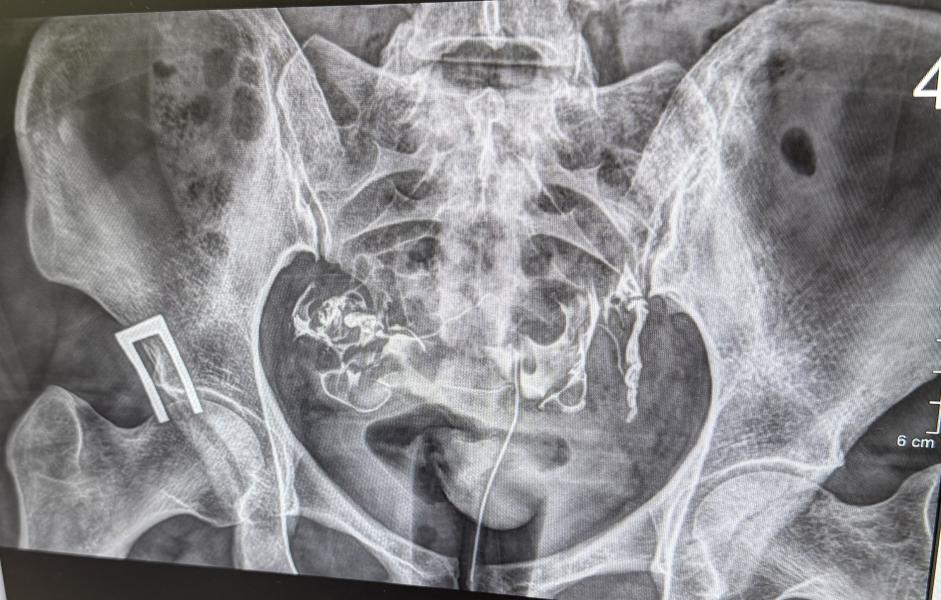

Сделала сегодня ГСГ маточных труб. Трубы проходимы, ни каких патологий нет. Три года назад на лапароскопии были с признаками хр.воспаления, где то расширены и извитые. Прикладываю рентген с контрастом. Может кто понимает, где там трубы? Я обвела красным по моему мнению трубы, синим матка 🤭

Не по теме ) знаете что мне всегда интересно? Эти трубки болтаются в разные стороны, яичники где-то там, когда овуляция происходит, как яйцеклетка проникает в них )) читала фимбрии как пылесос засасывают , но если они далеко расположены ))